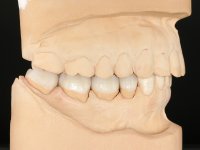

Paciente do sexo masculino, com 36 anos, não fumador. Fez tratamento ortodôntico e reabilitou esteticamente o sector anterior com restaurações em resina composta. As restaurações apresentavam um aumento vertical médio de 2 mm em relação o bordo incisal. Apresentavam-se esteticamente satisfatórias, mas com algumas fraturas incisais. O dente 1.5 apresentava um processo apical e o dente 2.6 apresentava tratamento endodôntico e uma lesão endo-periodontal. No maxilar inferior no local do dente 3.5 apresentava um implante com uma coroa aparafusada e o dente 8.5 ainda estava presente em boca com agenesia do dente 4.5. O paciente apresentava uma ligeira perda da dimensão vertical da oclusão provavelmente associada a um visível desgaste das superfícies oclusais. O periodonto era espesso e apresentava uma excelente higiene oral.

Após análise clínica e imagiológica foi proposto ao paciente recuperar a dimensão vertical da oclusão essencialmente à custa de incrementos oclusais inferiores utilizando “overlays” no sector posterior e facetas no sector anterior. A coroa aparafusada sobre o implante 3.5 seria substituída, no sentido de acompanhar este incremento. Na maxila o dente 2.6 teria extração indicada e posteriormente seria reabilitado com um implante e respetiva coroa. No sentido de reabilitar esteticamente o paciente duma forma minimamente invasiva, foi proposta a colocação de facetas feldespáticas no sector antero-superior. O objetivo de aumentar ligeiramente a D.V.O., teria como função “proteger” eficazmente o sector antero-superior.

Realizado o diagnóstico e tomada a decisão quanto ao tratamento a executar, tornou-se importante definir qual a sequência de trabalho a adotar no sentido de conseguir a reabilitação da D.V.O. (V.D.O), de forma progressiva e equilibrada. Na primeira fase fez-se uma pré-impressão da arcada inferior com silicone tipo “putty” e em seguida realizou-se o preparo dentário de todo o sector posterior. O preparo para os overlays foi feito coronalmente à linha amelo cementaria no sentido de ser o mais conservador possível. A impressão foi feita com técnica de dupla mistura após afastamento gengival realizado com pasta de caulino. A provisória foi realizada com resina composta de polimerização dual. Em laboratório foram realizados os overlays após se ter aberto ligeiramente (1,5mm) a D.V.O. nos modelos montados em articulador semi-ajustável. Simultaneamente o sector antero-inferior foi encerado no sentido de acompanhar este aumento da D.V.O. Também foi confecionada uma chave de silicone translucido para posterior confeção dos provisórios antero-inferiores. Em boca foi primeiro realizada a provisionalização dos dentes anteriores utilizando resina composta previamente aquecida após preparação das superfícies dentárias para a adesão. Foi colocado o dique de borracha para promover o isolamento absoluto e posteriormente foram colados os overlays. Em laboratório foi realizada nova chave de silicone para confecionar os provisórios antero-superiores. Seguidamente em boca foram preparados os seis dentes antero-superiores após colocação do fio de afastamento gengival. Feita a preparação adequada das superfícies dentárias foi realizada a impressão com técnica de dupla mistura e a respetiva provisória. Em laboratório foram confecionadas 6 facetas feldespáticas num modelo de trabalho tipo “Geller”. A provisória foi removida e as facetas foram coladas em boca utilizando um isolamento relativo competente. Esta opção foi tomada em virtude de uma prévia experiencia negativa com a colocação do dique de borracha na mandibula. Após a colagem dos laminados antero-superiores foram dadas 12 semanas para avaliar a adaptação do paciente à nova situação e então iniciar a confeção das facetas antero-inferiores. Após colocação do fio de afastamento gengival. foram feitos os preparos dentários adequados e em seguida foi feita a impressão. Também foi feita a preparação do dente 3.4 que, entretanto, tinha sofrido uma fratura do overlay. As facetas e a restauração do 3.4 foram realizadas num modelo de trabalho tipo “Geller”. Após remoção da provisória, as facetas foram coladas em boca, utilizando um isolamento relativo pelas razões apontadas anteriormente. Após colocação do trabalho o paciente foi reabilitado por outros colegas com um implante na zona do 2.6 e substituição da coroa aparafusada sobre o implante colocado no local do 3.5. Posteriormente surgiram fraturas nos overlays dos dentes 4.7 e 3.7 que foram reabilitados com overlays em Zr.